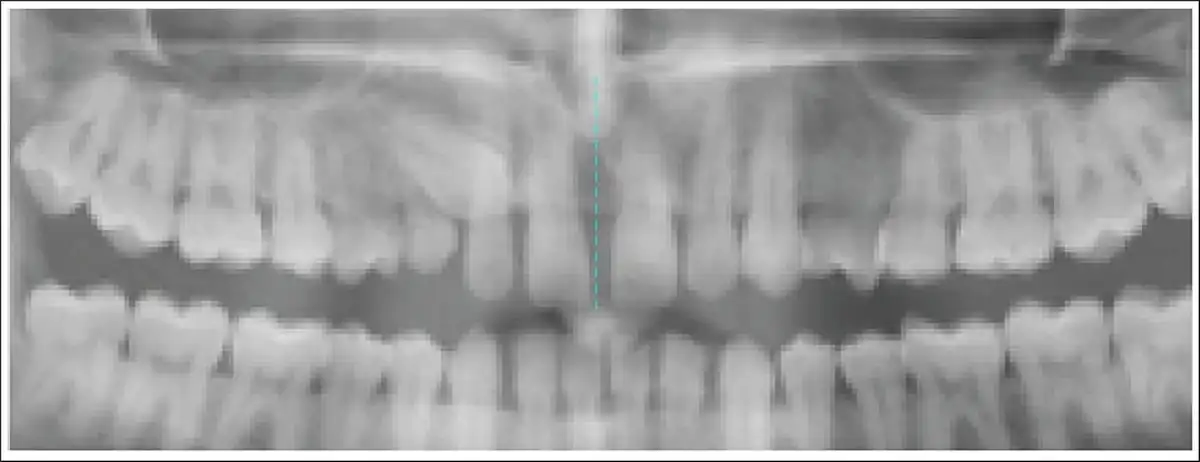

Step 2: Two points (anterior nasal spine and contact point between two maxillary central incisors) were marked to generate the midline (Figures 4 and 5).

Points for Generation of Midline.

Generation of Midline.

The midline was determined as line passing from the anterior nasal spine through the interincisal contact of the permanent maxillary central incisors. Angulation exceeding 31° was indicative of unfavorable canine impaction.